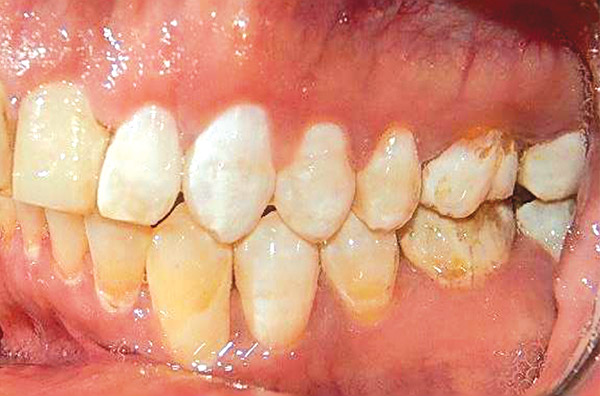

Respecto a los estudios finales intraorales, en las fotografías podemos observar la coincidencia de líneas medias dentales (Figura 19), la clase I molar y canina bilateral (Figura 20 y 21).

Figura 20.

Figura 21.

Finalizado el tratamiento se realizaron carillas provisionales en el maxilar superior de los diente 15, 14, 13, 12, 11, 21, 22, 23, 24, 25 para su posterior rehabilitación (Figura 22) el overjet y overbite adecuado.